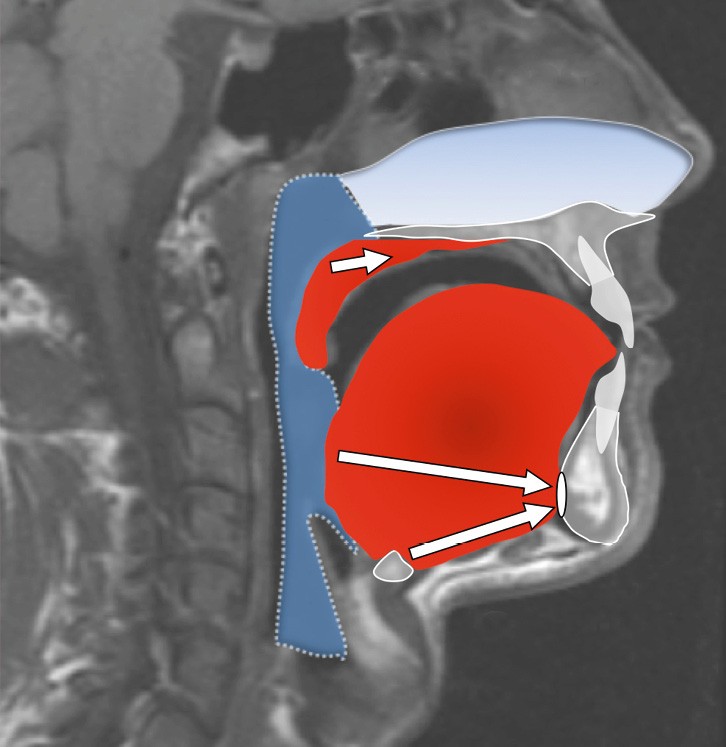

Le collapsus pharyngé à l’origine du SAOS peut résulter de mécanismes variés, souvent associés. L’hypertrophie des tissus mous (amygdales, base de langue, parois pharyngées) en est l’une des causes possibles, fréquemment liée au surpoids observé dans cette pathologie.

L’étroitesse squelettique peut également être impliquée (rétromandibulie, hyperdivergence, endognathie) [1] (fig. 1-4).

Plusieurs approches chirurgicales ont été décrites : les chirurgies des tissus mous visant la désobstruction pharyngée, les chirurgies squelettiques destinées à élargir le calibre pharyngé et, plus récemment, les interventions visant à augmenter le tonus musculaire lingual par stimulation du nerf hypoglosse (fig. 5).